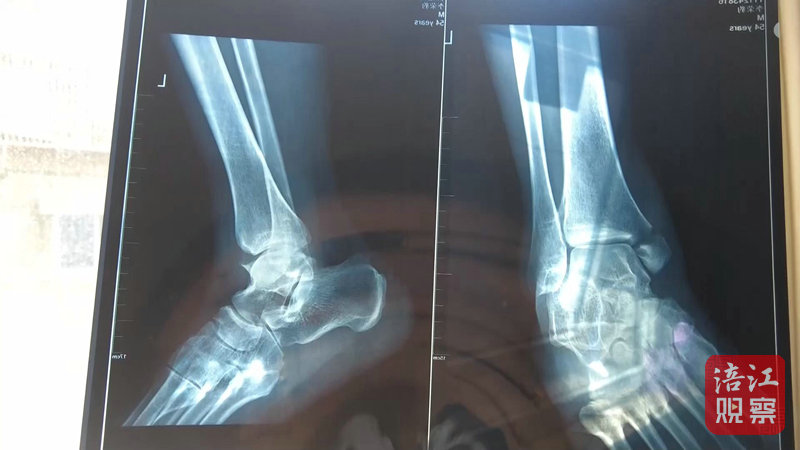

4月22日,記者來到綿陽市骨科醫院,病房內,李先生正在進行術后上下床的康復訓練。李先生的主治醫生介紹,李先生因左內踝骨折入院,手術一周后傷口愈合良好,病情穩定,目前已轉入康復科進行康復功能鍛煉。